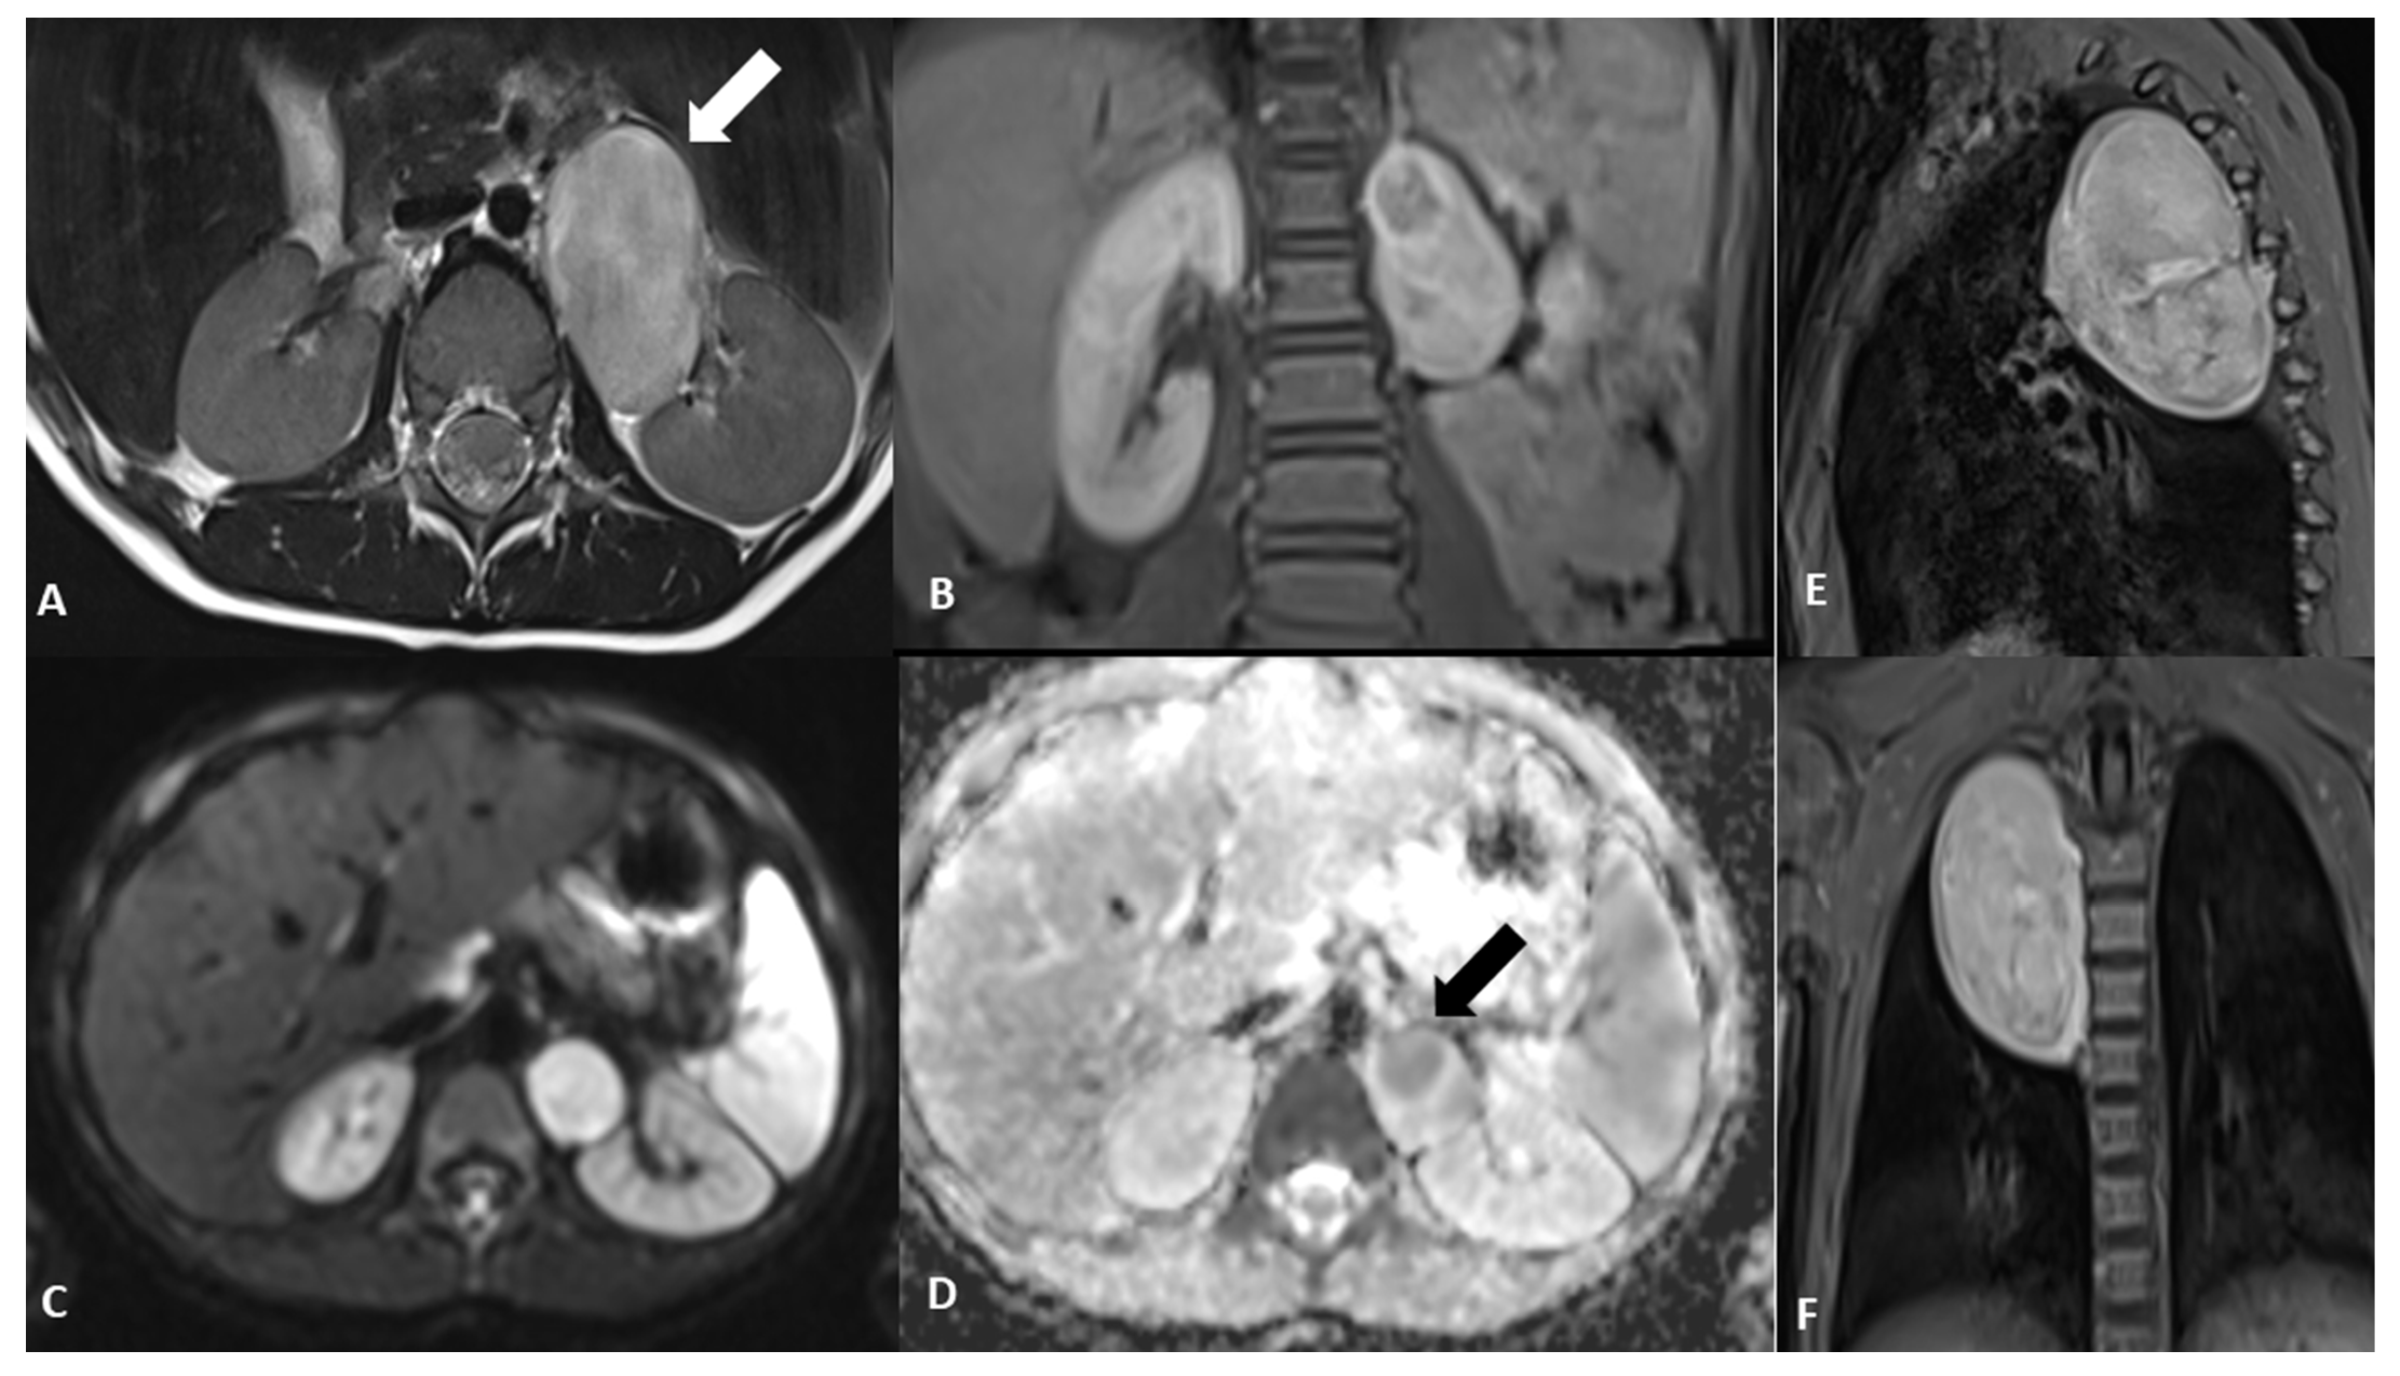

Figure 2. Magnetic resonance imaging (MRI) at baseline. The exam was performed in order to complete the framing and precisely define the anatomic relationships, which confirmed the two clear-edged, capsular, expansive formations located in the posterior mediastinum and in the left anterior paravertebral abdominal site, in the absence of intraspinal extension. An axial T2-weighted image shows the abdominal paravertebral mass (A) that presents inhomogeneous enhancement after contrast administration (B). The thoracic lesion in the posterior mediastinum shows a similar perfusion pattern, as shown in the coronal and sagittal T1-weighted images (E,F). (C) MRI axial diffusion-weighted imaging (DWI) shows a hyperintense rounded area with low apparent diffusion coefficient (ADC) value in the upper portion of the abdominal mass, as shown in (D) (arrow). Blood tests and urinary catecholamines were within normal limits. In order to determine a diagnosis of certainty, an echo-guided biopsy of the lesion located at the level of the posterior mediastinum was performed, as it was more easily reached than the abdominal mass; histopathological features were finally consistent with a GNBI, with the presence of Schwannian stromal development occupying >50% of tumor tissue [1] (see also histological image).